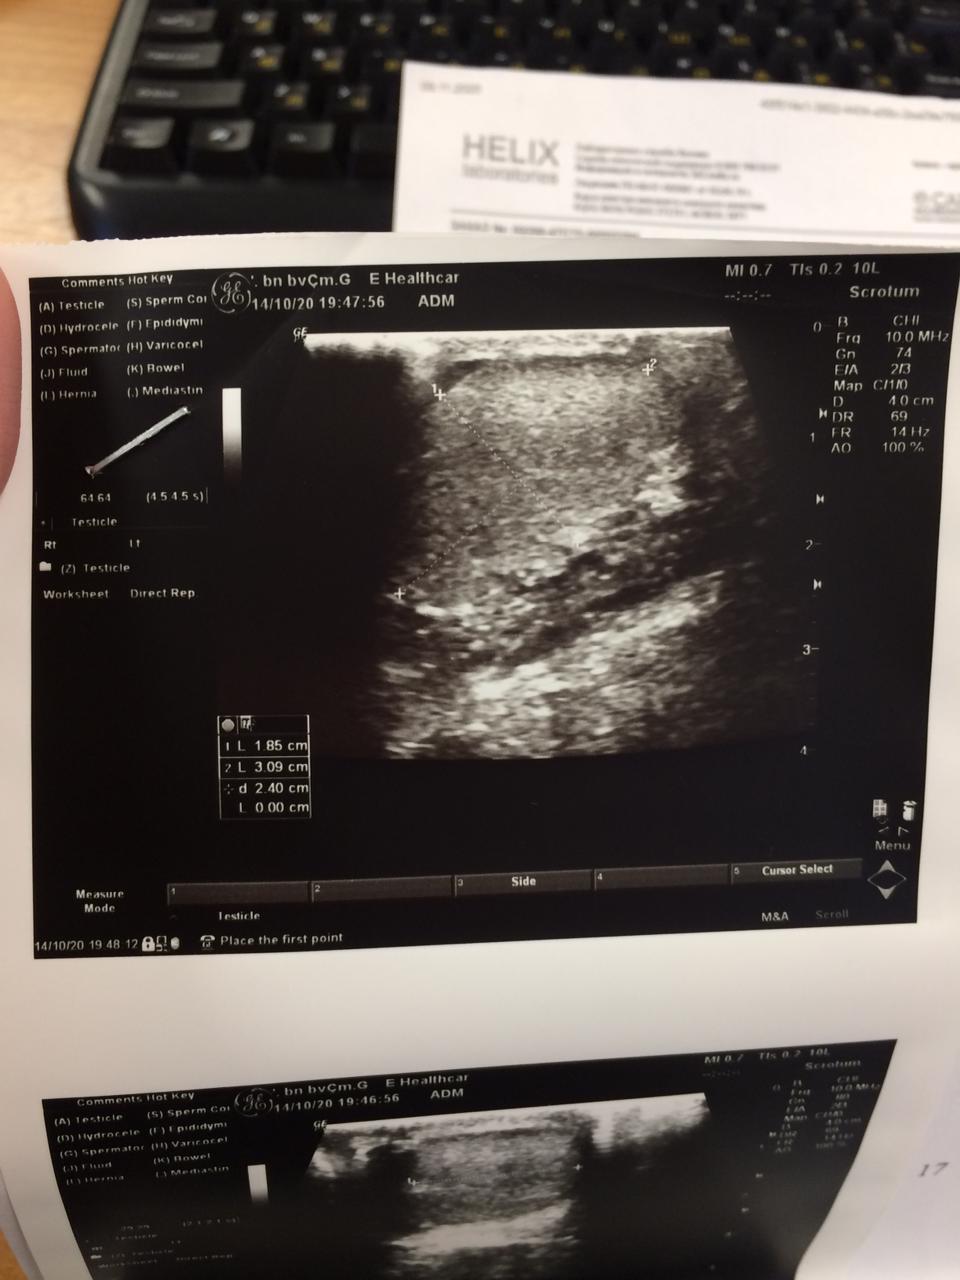

Здравствуйте!В данном случае наблюдается повышение ЛГ и ФСГ, на фоне чего - гипоплазия яичек. Тут надо понимать - какой срок этой проблеме. И как изменился объём яичек в динамике. Безусловно, можно предпринять попытку коррекции ситуации. Но надо понимать, что нормальных показателей спермы вряд ли удастся достичь. Речь идёт о возможности ЭКО( при получении хотя бы единичных сперматозоидов). Обращайтесь в клинику ЭКО. Удачи!